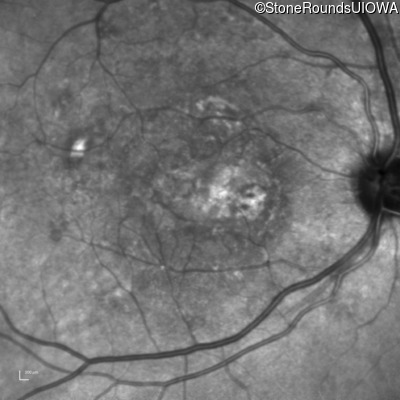

AR Stargardt Disease (IIA)

Age at visit: 59 years (Visit 3)

This 59 year old woman first noticed vision loss in her right eye a few months earlier. She has a cousin with Rhodopsin-associated RP.

Diagnosis & molecular findings

Disease Gene Allele 1 variant(s) Allele 2 variant(s) Inheritance mode

AR Stargardt Disease ABCA4 Arg219Thr AGA>ACA Gly863Ala (G)GA>(G)CA AR